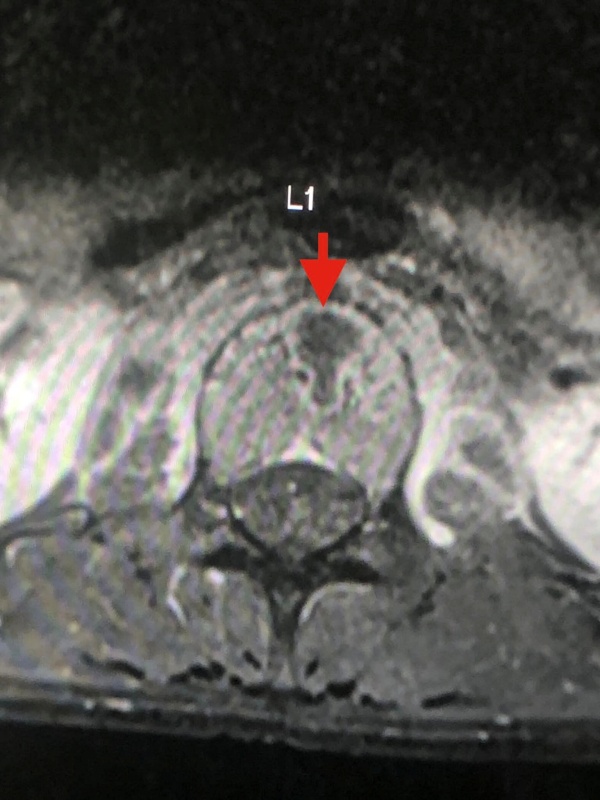

อย่างไรก็ตาม เมื่อลองทำ MRI กระดูกสันหลังส่วนเอว กลับพบความผิดปกติ และมีความเป็นไปได้ที่เธอจะเป็นวัณโรคของกระดูกสันหลังส่วนเอวชิ้นที่ 1 และสงสัยว่าจะมีการอักเสบรอบ ๆ เนื้อเยื่อกระดูกสันหลังส่วนเอวชิ้นที่ 1 และ 2 ร่วมด้วย จึงทำการเจาะเนื้อเยื่อรอบกระดูกสันหลัง ส่งตรวจย้อมเพื่อหาเชื้อวัณโรค และให้ผลลบ จากนั้นก็รอเพาะเชื้อวัณโรค ส่งตรวจพยาธิวิทยา พบว่าเนื้อเยื่อตายและไม่พบมะเร็ง และสรุปได้ว่า เธอเป็นวัณโรคที่กระดูกสันหลัง